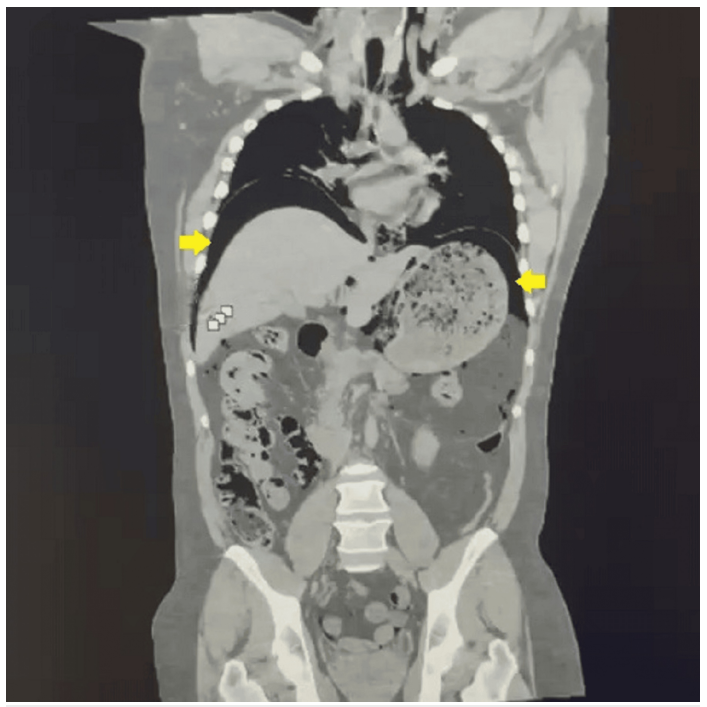

Computed tomography of the abdomen confirmed a massive pneumoperitoneum consistent with hollow viscus perforation.

Emergency diagnostic laparoscopy revealed abundant free air in the abdominal cavity and a 3-cm perforation on the anterior surface of the stomach.